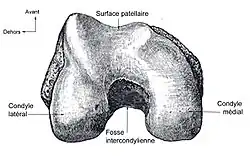

(vue inférieure fémur droit)

- l’extrémité inférieure du fémur qui a la forme de deux roues accolées : les condyles ;

Les facteurs anatomiques sont soupçonnés déjà depuis longtemps. La résistance à la rupture d'un LC dépend directement de sa largeur, qui varie d'un individu à l'autre. Dans une étude anthropométrique, les LCA du genou controlatéral intact de patients victimes d'une rupture de LCA ont été comparés avec ceux d'individus de même poids corporel. Les volumes des LC ont été déterminés par IRM. Dans le groupe des blessés, le volume des LCA contralatéraux était en moyenne 1 921 mm3, tandis que dans le groupe de contrôle, il était de 2 151 mm3. Les auteurs de l'étude en concluent que les différences anthropométriques des volumes – et de la largeur qu'on en déduit – des LC ont une influence directe sur la probabilité d'une rupture de LC sans agression externe[49]. Déjà dans des études précédentes, on a établi une corrélation entre cavité ligamentaire du fémur (notch intercondylaire : voir figure) étroite, liée à des ligaments plus étroits, et un risque plus élevé de rupture de LC[50],[51],[52],[53],[54],[55]. Cependant on n'est pas arrivé à un consensus scientifique, parce que d'autres études aboutissent à des résultats opposés[43],[56],[57]. Par rapport aux hommes, les femmes ont une cavité ligamentaire plus étroite, ce qui pourrait expliquer une incidence plus élevée des ruptures de LC chez les femmes[58],[59].